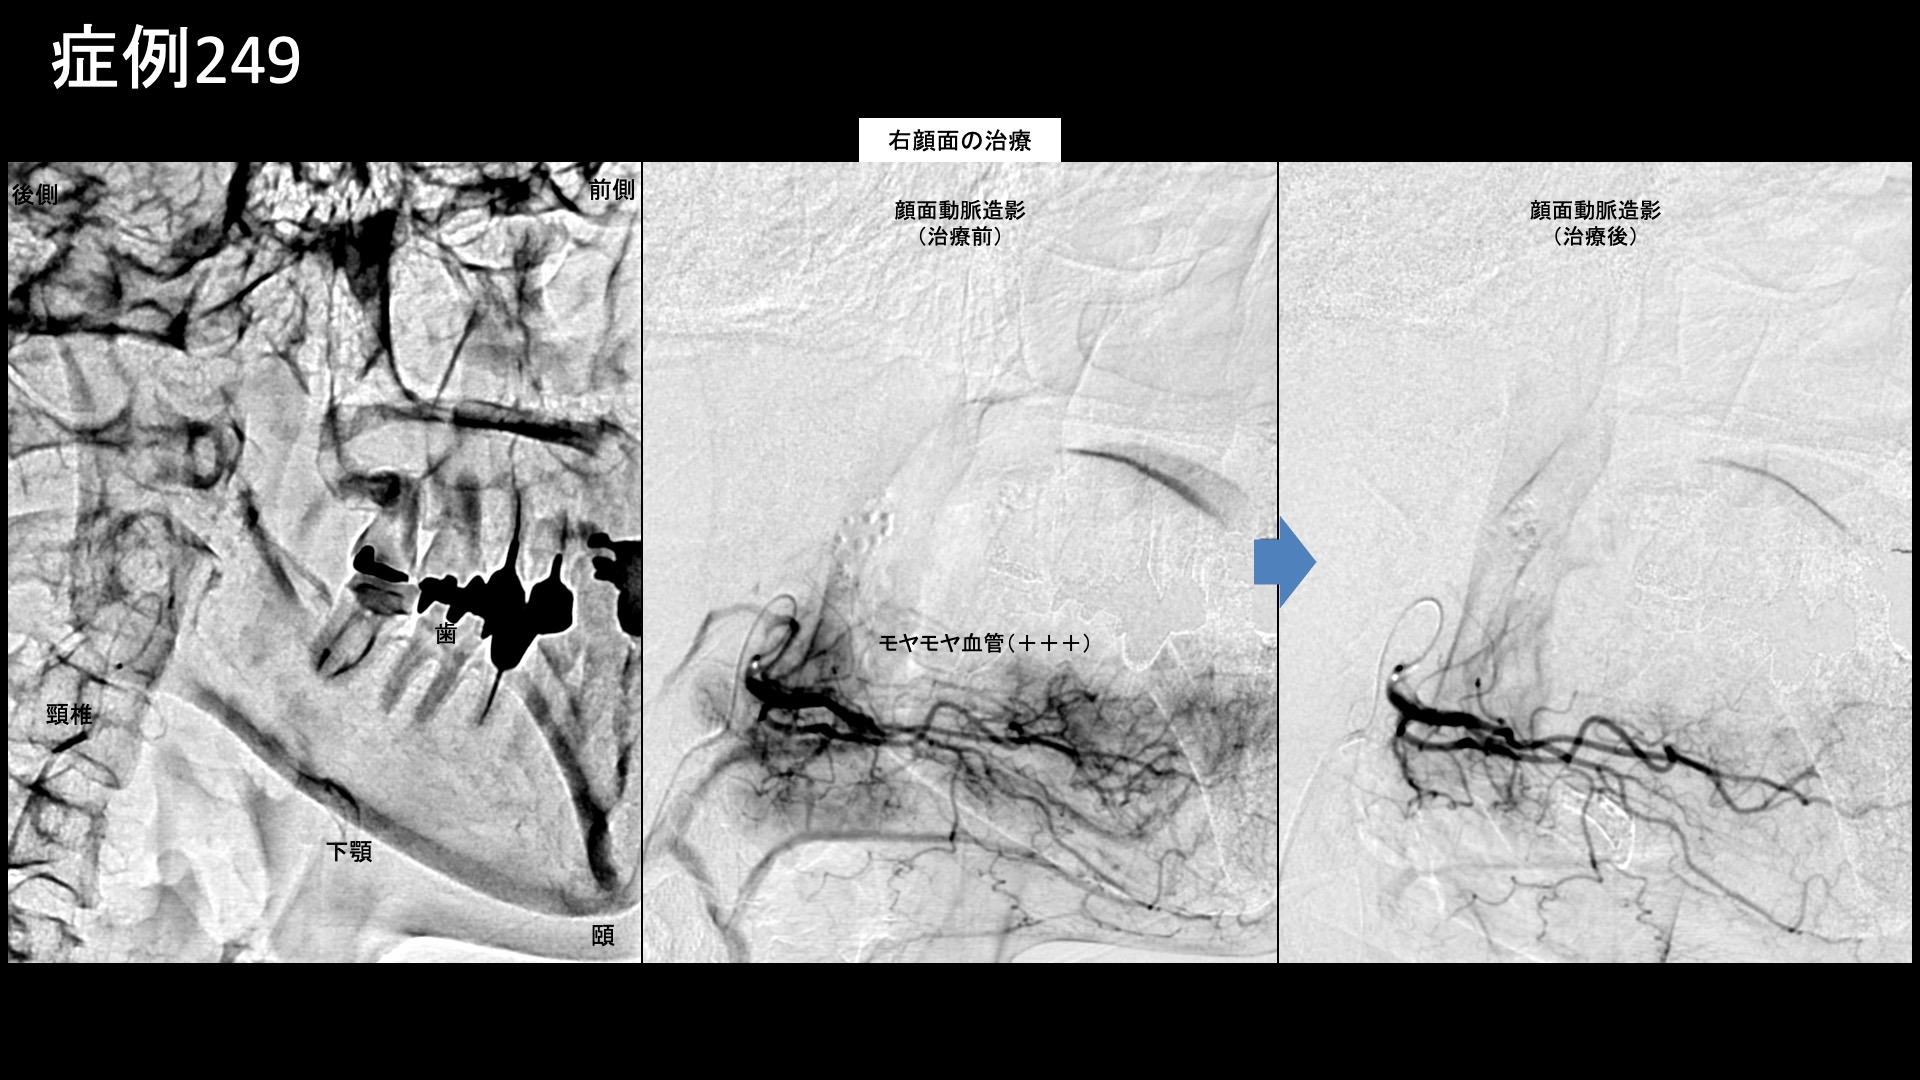

血管造影を行うと、顎動脈、顔面動脈でモヤモヤ血管が濃染像として描出されました。いずれも、頬に一部が灌流する血管です。治療中は、同部に一致して、再現痛および、色調変化が見られました。薬液を投与すると、一時的に皮膚の色調が白くなりその後赤みが戻り、元の色調に回復するという変化が起きます。これらを確認することで、治療標的部位に十分な治療ができたかどうかを確かめます。治療後モヤモヤ血管は画像上速やかに消失しました。その他複数箇所の治療を行い終了しました。

治療前画像:損傷を受ける、あるいは繰り返しのストレスにより発生した異常な新生血管

治療後画像:カテーテルを用いて塞栓物質を血管内に投与し新生血管を塞いだ状態